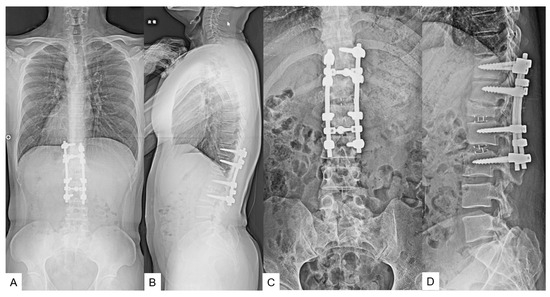

2.5. Postoperative Images

2.6. One Year Follow-Up

3. Case 2: 33-Year-Old Male, Tethered Cord Syndrome, Conventional Technique